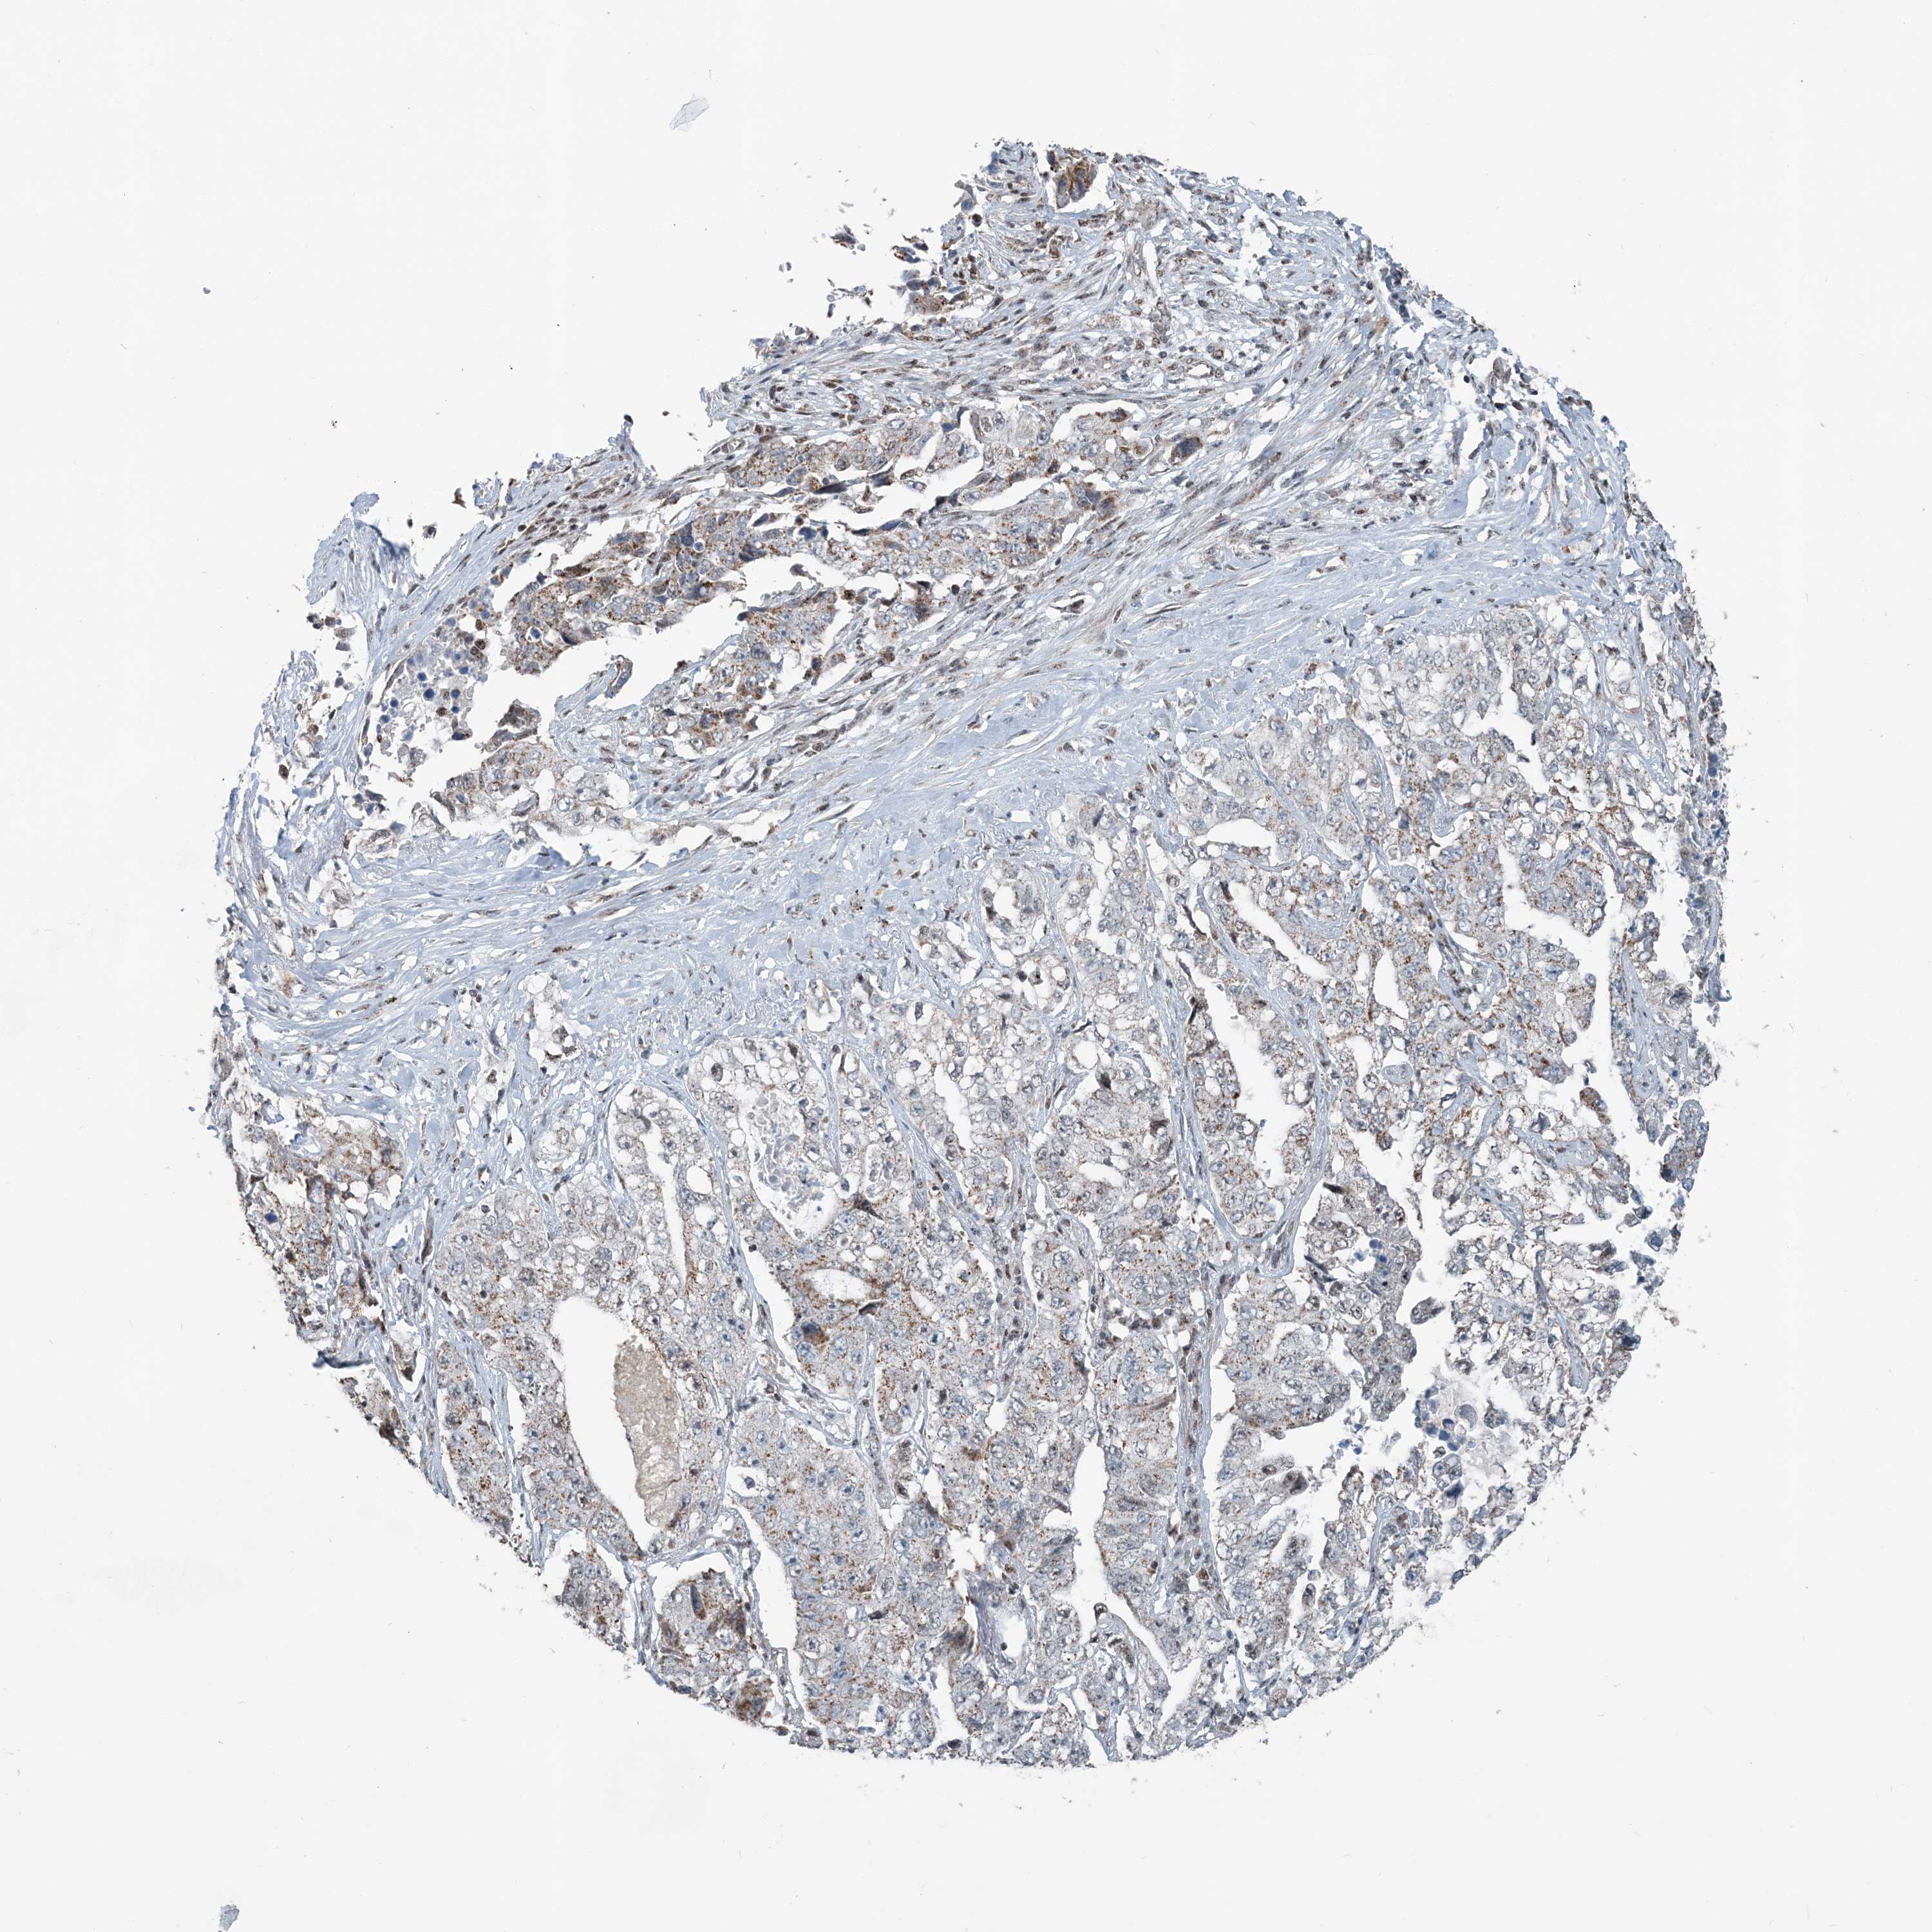

CANCER LUNG CANCER Show tissue menu

SUCLG1 is not prognostic in Lung Adenocarcinoma (validation)

Best expression cut offi

Based on the FPKM value of each gene, patients were classified into two groups and association between prognosis (survival) and gene expression (FPKM) was examined. The best expression cut-off refers the FPKM value that yields maximal difference with regard to survival between the two groups at the lowest log-rank P-value. Best expression cut-off was selected based on survival analysis .

When clicking on this number, the vertical dashed line indicating cut-off, the interactive survival plot, and the Kaplan-Meier curve will be adjusted to show results based on the best expression cut-off.

: 65.44

Median expressioni

Median expression refers to the median FPKM value calculated based on the gene expression (FPKM) data from all patients in this dataset. When clicking on this number, the vertical dashed line indicating cut-off, the interactive survival plot, and the Kaplan-Meier curve will be adjusted to show results based on the median expression.

: N/A

P scorei

Log-rank P value for Kaplan-Meier plot showing results from analysis of correlation between mRNA expression level and patient survival.

N/A

5-year survival highi

5-year survival for patients with higher expression than the expression cutoff.

For melanoma and glioma, 3-year survival is shown.

5-year survival lowi

5-year survival for patients with lower expression than the expression cutoff.

TCGA RNA samplesi

RNA-seq data is reported as average FPKM (number Fragments Per Kilobase of exon per Million reads), generated by the The Cancer Genome Atlas (TCGA) .

Normal distribution across the dataset is visualized with box plots, shown as median and 25th and 75th percentiles. Points are displayed as outliers if they are above or below 1.5 times the interquartile range. FPKM values of the individual samples are presented next to the box plot.

Average pTPM 83.1

Number of samples 105